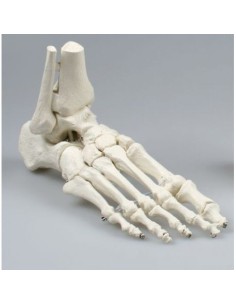

Dal cranio in 22 parti con incastri magnetici ai modelli di colonna vertebrale, da quelli di articolazioni a quelli di cuore, ogni pezzo della nostra collezione è progettato per un’immersione totale nello studio dell’anatomia umana. I nostri modelli, realizzati tramite scansioni di ossa vere, garantiscono un’esperienza tattile autentica e una fedeltà di peso quasi identica agli originali.